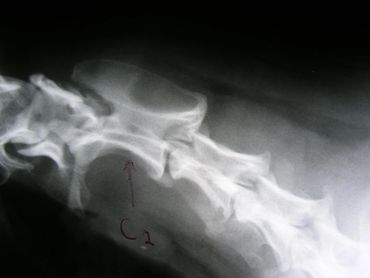

The spinal column is made up of four major vertebral regions: cervical (neck), thoracic (mid back), lumbar (low back) and sacral (pelvic). Dogs have seven cervical, thirteen thoracic, seven lumbar and three sacral vertebrae. There are also variable numbers of coccygeal or tail vertebrae. Intervertebral disks are located between the vertebral bodies starting at the second and third cervical vertebrae (C2-3) and extending to the seventh lumbar and first sacral vertebrae (L7-S1). The three sacral vertebrae are fused and therefore do not have disks. Intervertebral disks are present between the coccygeal vertebra as well, but are of little clinical significance.